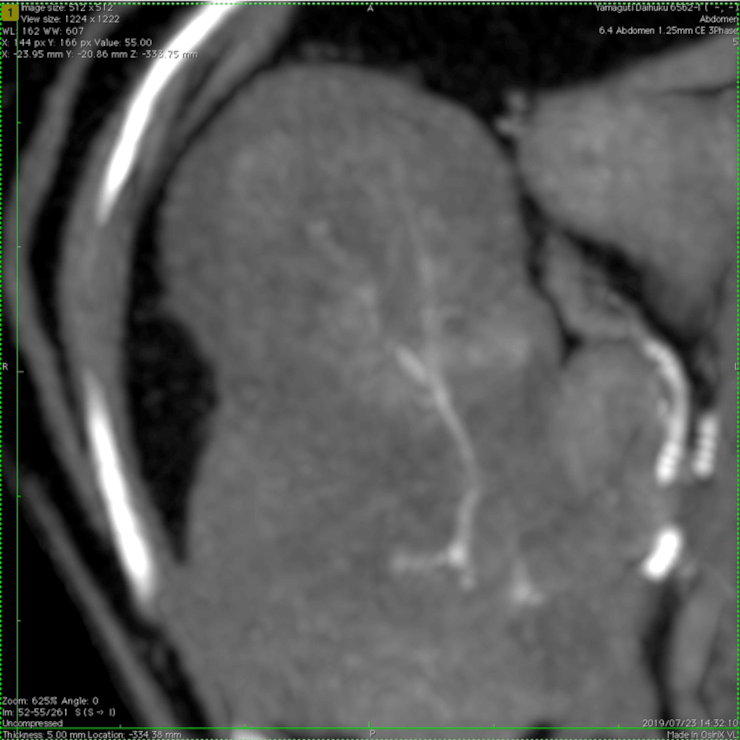

【実施症例】肝臓腫瘍に対する動注療法

柴犬、12歳、雄。

肝臓内側左葉に発生した巨大肝臓腫瘍。高齢で手術リスクが高いため、肝臓腫瘍に対して TACE(肝動注化学塞栓療法)を実施した。 実施から1ヵ月後のエコー検査で、腫瘍の若干の縮小と内部の壊死が認められた。

肝臓腫瘍の3D・CT画像

肝動注化学塞栓療法

実施前

実施後